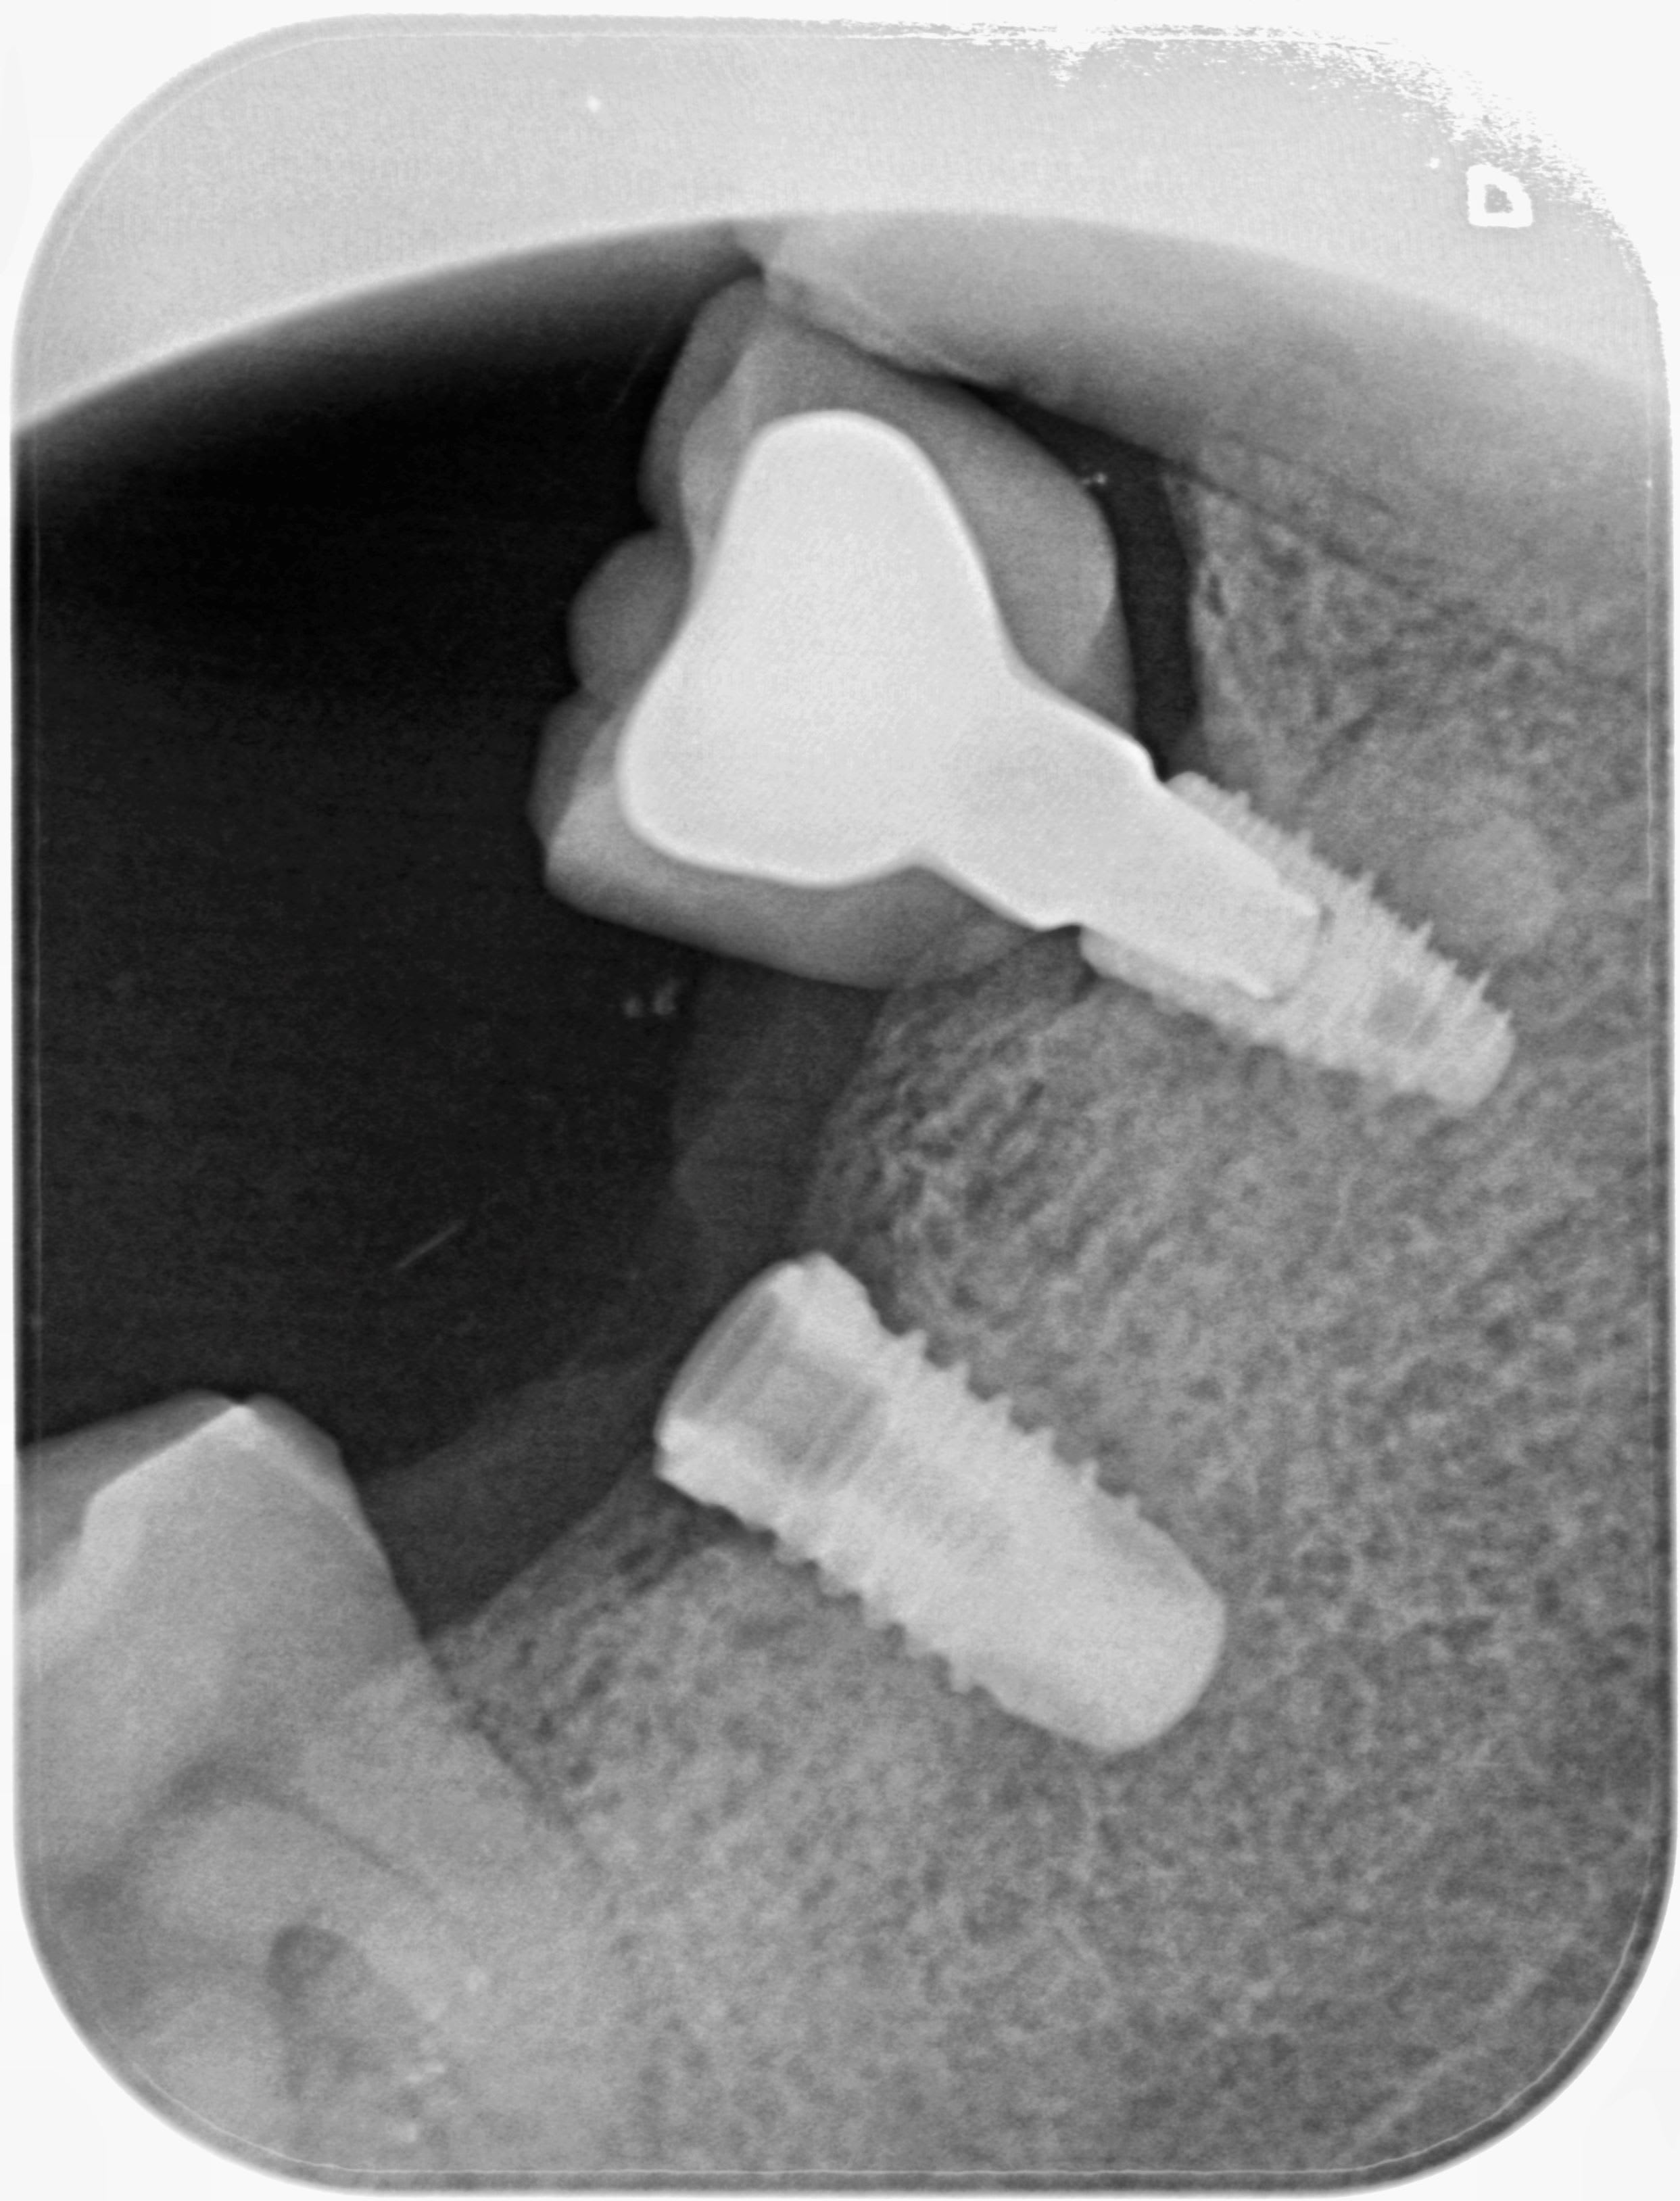

Qqun (Pluton par exemple?) pourrait me donner la référence de cet implant?

J’imagine que c’est pas pour celui qui a une couronne et qui est un Biotech kontact ….

Rien trouvé pour l’instant pour l’autre….je vois rien sur la connexion à la radio

Essaye de démonter le pilier pour me donner des infos sur la connexion (externe/interne/hexagone/octogone, etc…..)

Ahhhh avec cette radio c'est tout de suite plus facile

https://www.spotimplant.com/fr/implants-dentaire/sweden-martina/kohno

Oups, pardon, j’ai fait une boulette…..en regardant la première radio j’ai eu un flash….

C’est pas un sweden martina mais un Thommen

https://www.spotimplant.com/fr/implants-dentaire/thommen/spi-element